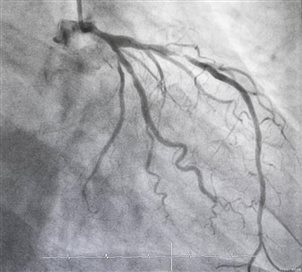

冠脉造影是微创介入检查,经手腕或大腿根部穿刺血管,将导管送至冠状动脉注入造影剂,动态观察血流情况,是诊断冠心病的“金标准”。结果准确可靠,若发现重度狭窄,可同期进行支架植入等治疗。适合症状典型的心绞痛、急性心肌梗死、疑似严重冠脉病变,以及需要制定手术方案的患者。缺点是有创操作,需住院,存在穿刺、出血等轻微风险。